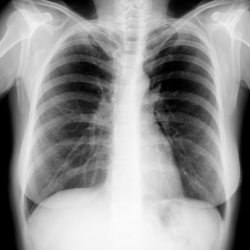

Человек 45 лет. ничего не беспокоит. Профилактически сделан снимок. Какая патология каково ваше мнение?